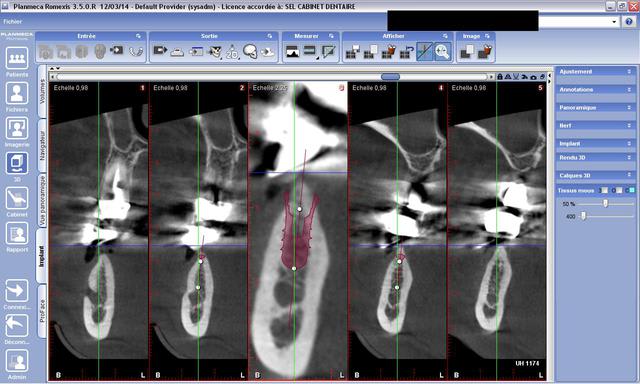

Tu mets le diamètre qui te permet d'avoir 1mm en vestibulaire et 1 mm en lingual (sinon rog)... Mais petit conseil tauraude...

Non, un ancrage bicortical est mieux pour ton implant (selon davarpanah), en tous cas ça fait pas de mal.

Il faut juste tarauder pour éviter de forcer pendant le vissage de ton implant, et faire chauffer l'os qui est de type 1 ici, très corticalisé.